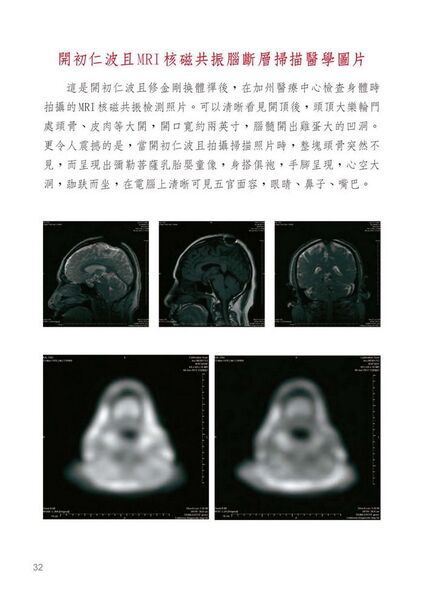

《解脫大手印》—必須要看懂的前導文 擁有虛名的第四世祿東贊行人講述__ 比如開頂成就解脫就是鐵證,我看到開初仁波且和妙空法師是真開了頂的,而不是那虛名的所謂開頂插吉祥草,他們是跟我一樣受《解脫大手印》金剛換體禪境行灌頂開的頂。在灌頂當時,頭頂肉與骨的表顯則是完好無異樣變化,卻能開能關,在醫學的照片檢視上清清楚楚就是開頂了,並且照到了靈識出體的剎那氣相體,確實證明肉與骨頭、腦膜、腦髓都不見了一到二指寬,其中一位出現螺旋狀洞口,一條線一直深入大腦中心,另一位則洞有雞蛋大小,直入腦底,他們二位才是真金大聖德、大王臣啊!無論什麼人所講空洞的理論都是代表不了實際成果的,所以千萬不要迷信那些說假話空洞理論派的假聖德。